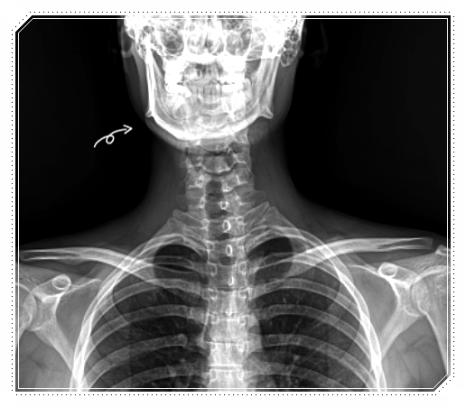

턱관절 통증은 턱에서 시작된 것처럼 느껴지지만,

실제로는 안면, 두개골, 목, 골반까지 이어지는

전신 균형의 문제인 경우가 많습니다.

Q. 그럼 턱 말고 어디까지 봐야 될까요?

저는 턱관절통증치료병원을 찾아오신 분들을 볼 때

항상 “왜 여기까지 통증이 왔을까”를 먼저 살펴봅니다.

- 안면 긴장

- 목의 정렬

- 골반의 기울기

- 걷는 방식

이러한 요소들을 함께 확인합니다.